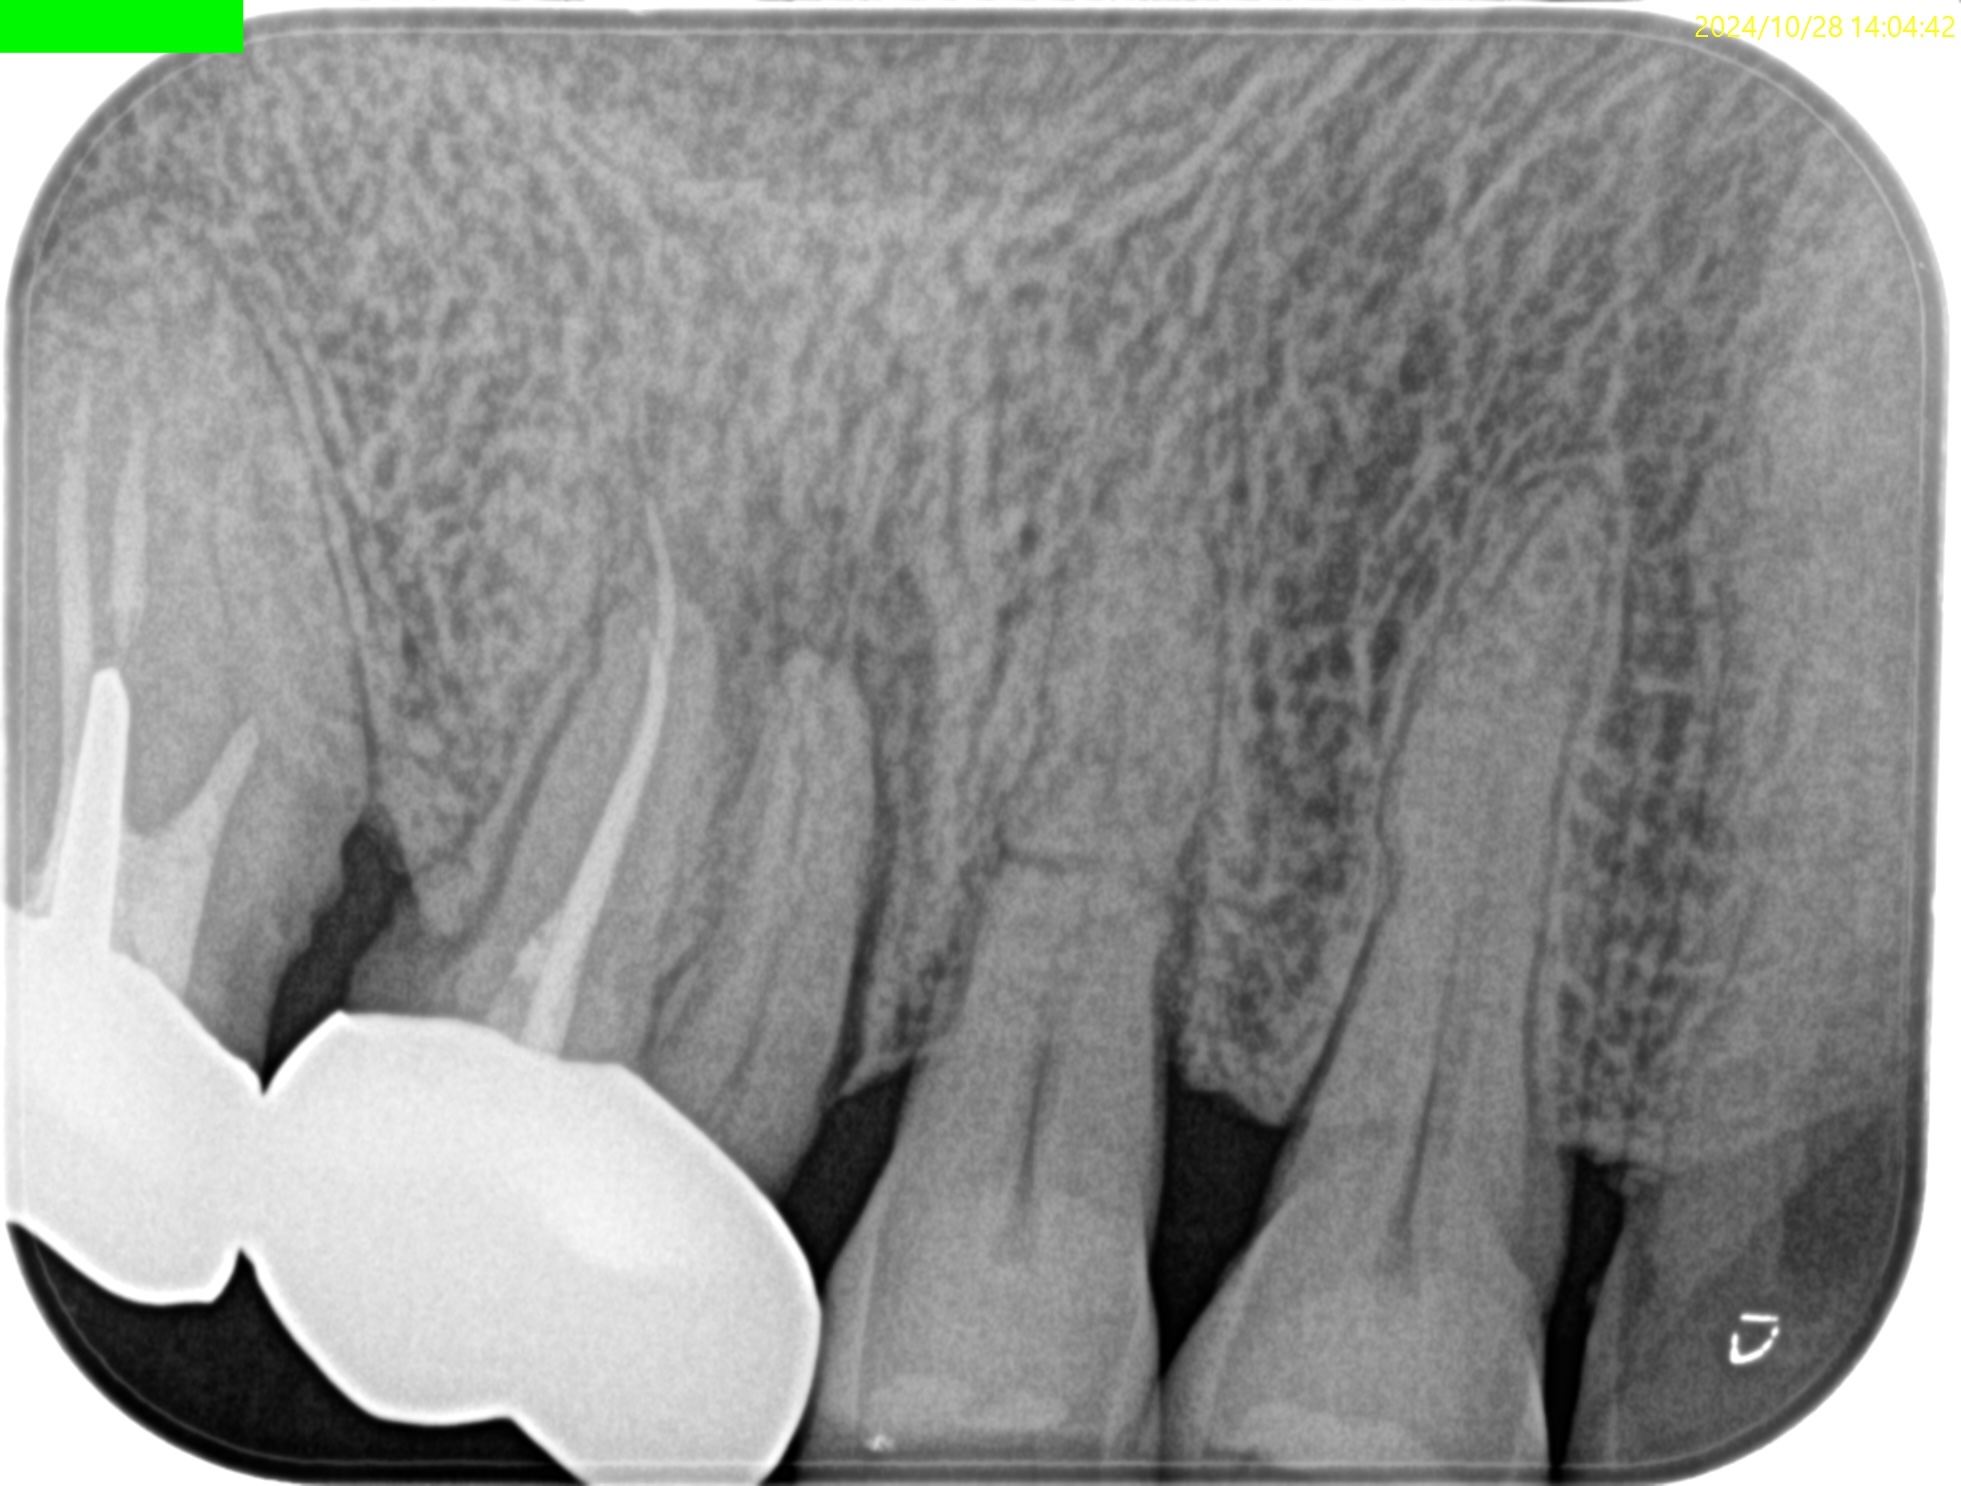

PA(2024.10.28)

#3にSinus tractと圧痛がある。

が、今回ご紹介するのは#4である。